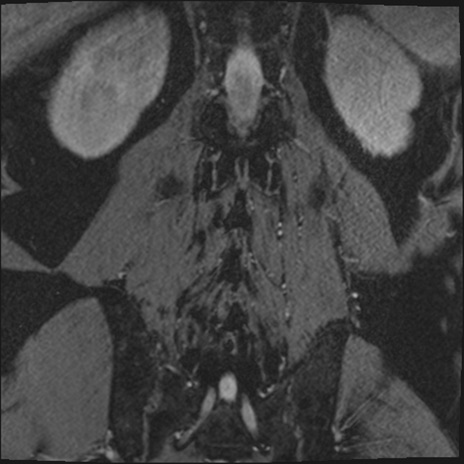

【整形】TIPS症例2 腰椎MRI 3D(冠状断像)

【症例】70歳代男性

【主訴】左下肢痛

【現病歴】2週間前くらいから腰痛、左下肢痛あり。左臀部から大腿、下腿外側のしびれが常時ある。歩行とともに同部位の痛みあり。

【身体所見】Lasegue70-/60+、Bragard-/±、PTR ±/±、ATR -/-、IP 5/5、TA 5/4、TS 5/5、EHL 右第1足趾なし/3、FHL 5/5、hypersthesia(-)、足背動脈触知良好

異常所見と診断は?